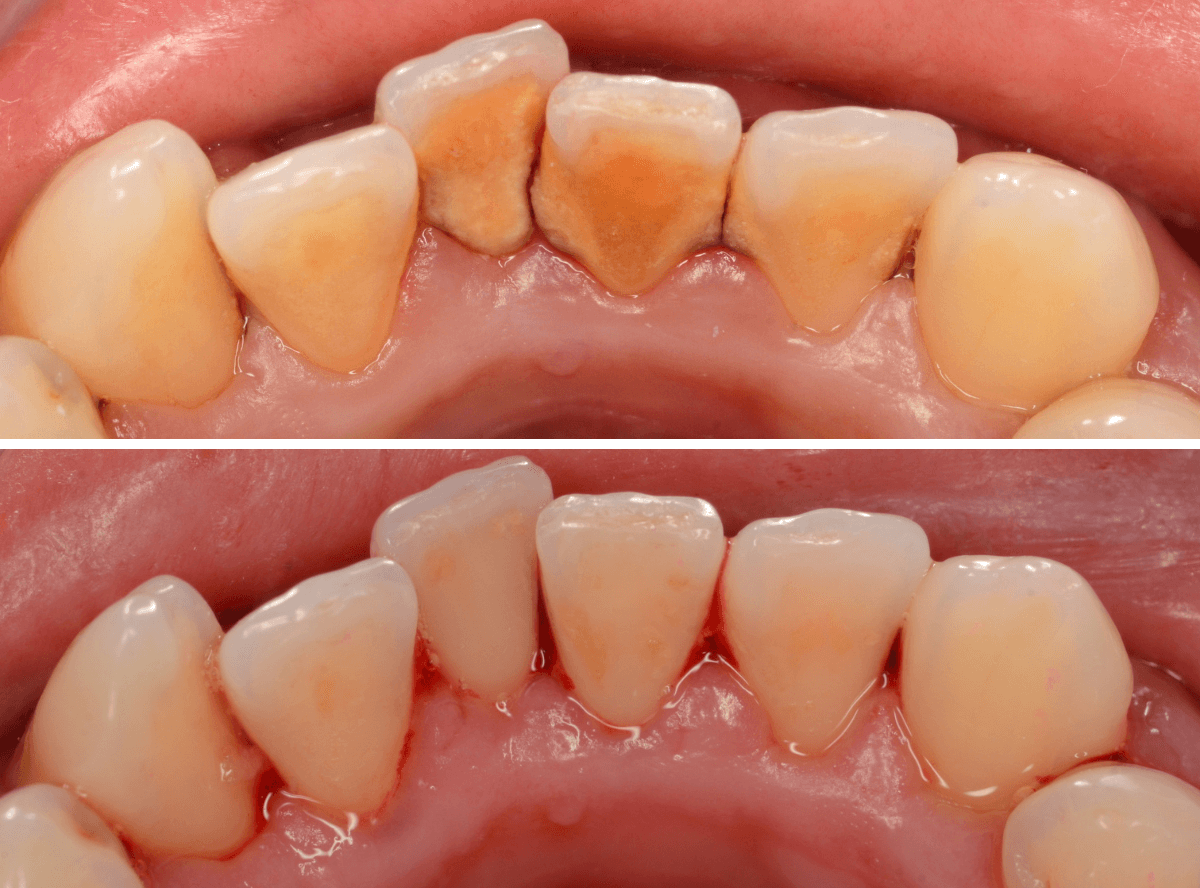

Case.4「歯の周りの黒い物を取って欲しい」という患者さん

今回は、「歯の周りの黒い物を取ってほしい」という訴えの患者さんのケースです。

着色かな、と思い口の中を拝見すると、歯の表面まで露出した縁下歯石でした。

当院は、(現在のところ)比較的若い患者さんが多いので、ここまでハッキリ縁下歯石が露出しているケースは珍しいです。

患者さんには、歯周病の基本的な説明とブラッシング指導をした後、まず下の歯の歯石除去から始めました。

ブラッシング指導・下の前歯の歯石除去直後の写真です。

これだけでも、かなり改善したかと思いますが、これだけの縁下歯石の量ですから、一回の歯石除去で全て取り切れるはずがありません。

根気よく、歯石除去を続ける必要があります。

ビフォー・アフターです。

後日、上の前歯の歯石除去を行いました。

下の前歯の歯肉も改善されてきていますね。

上の歯だけで、これだけの縁下歯石がとれました(まだ歯肉の奥には残っていると思います)。

一度では取り切れません、時間をかけて取っていく必要があります。

かなり歯肉の改善がされていますが、まだしばらく治療は続ける必要があります。